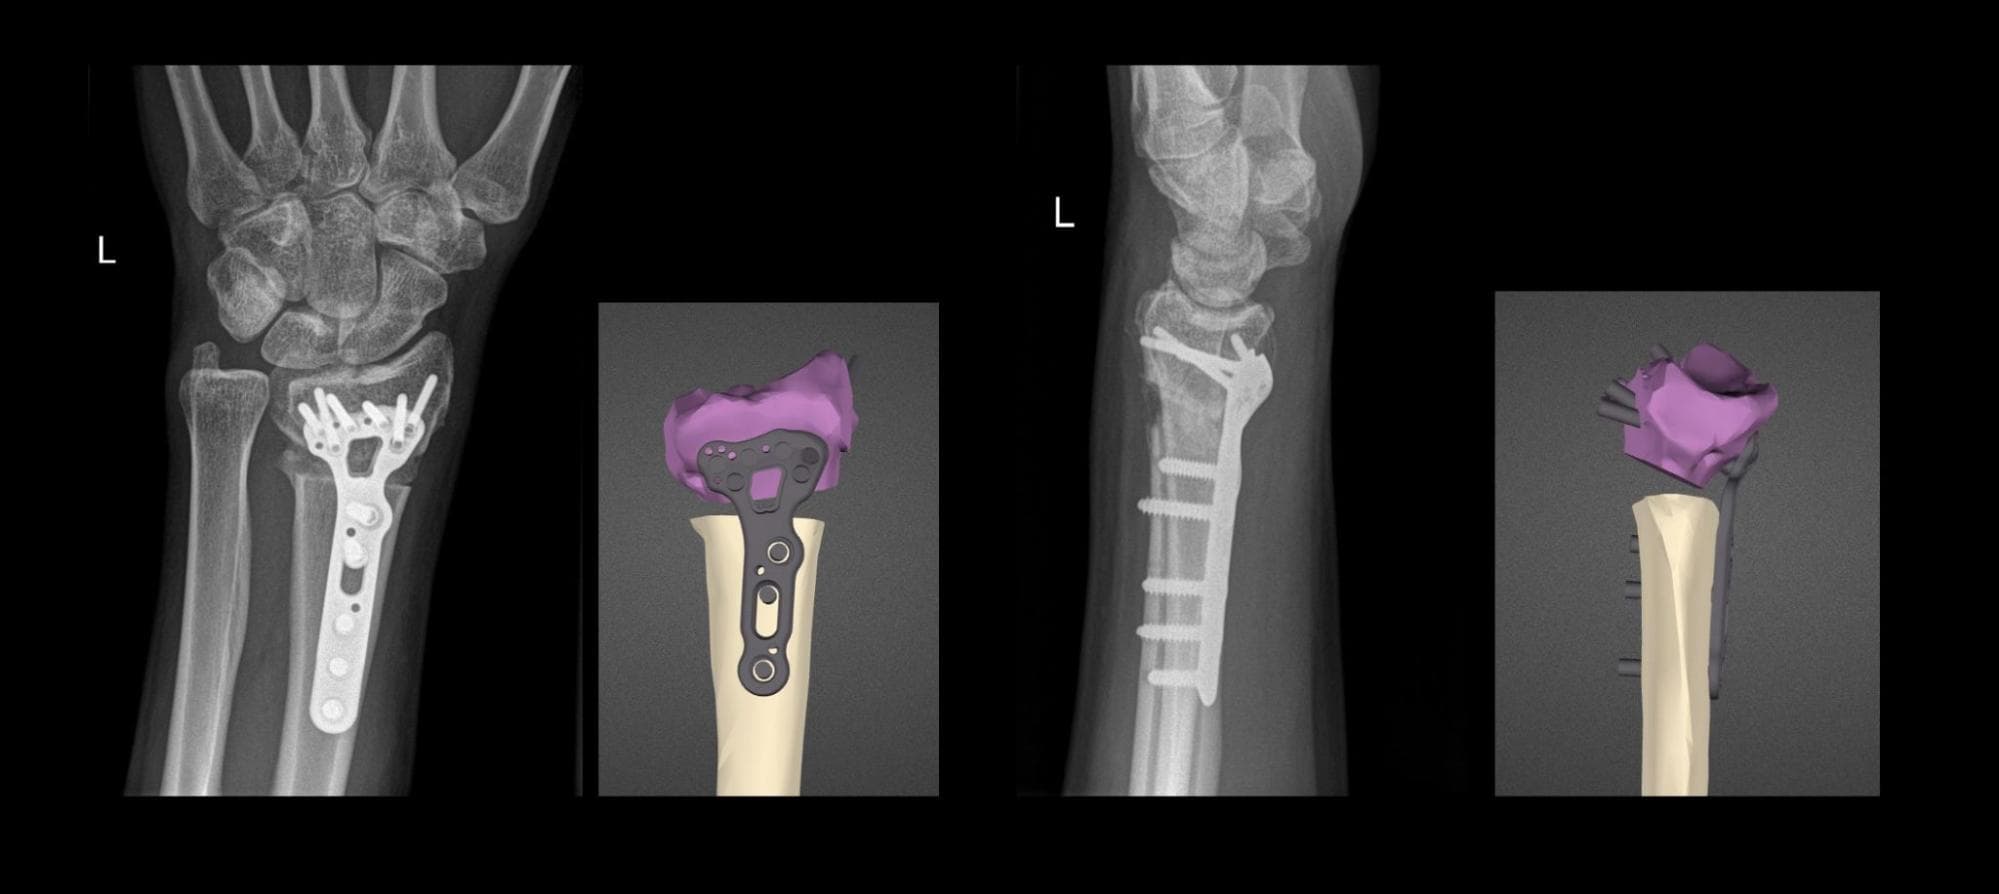

SLS 3D Printed Anatomical Models and Surgical Guides for Improved Fracture Treatment and Complex Osteotomies